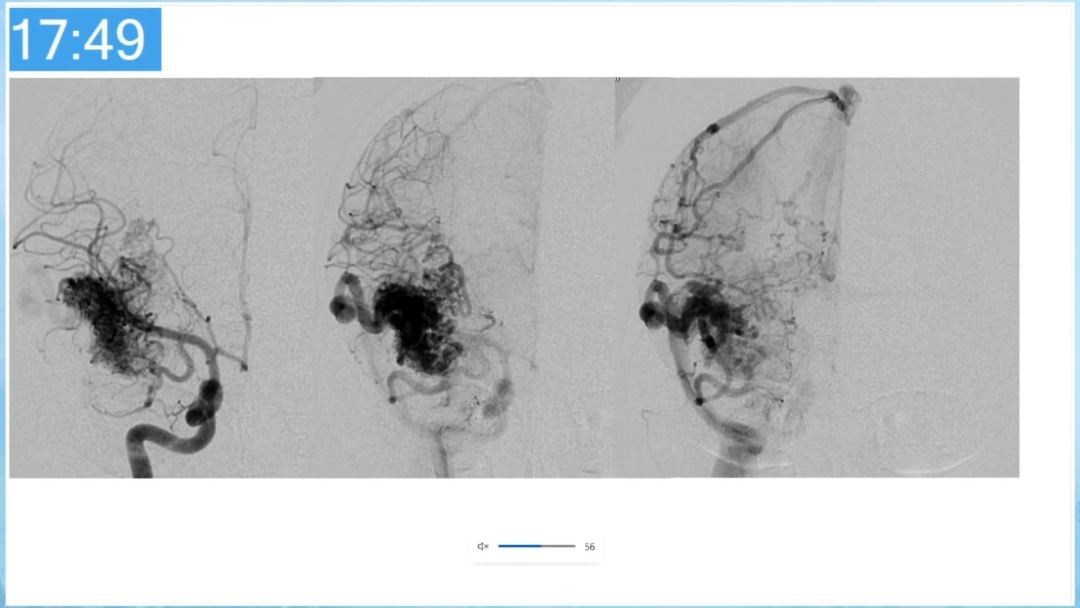

本期为大家特别分享:空军军医大学唐都医院邓剑平教授的精彩会议内容《颅内动静脉畸形的复合手术治疗》,欢迎大家阅读和分享!